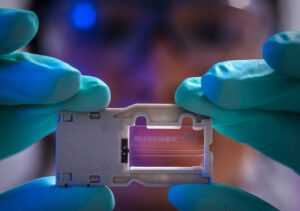

研究チームが使ったのは「高解像度質量分析法(High-resolution mass spectrometry)」という技術だ。これは化学物質の「指紋」を極めて細かく読み取る方法で、従来の検査では見えなかった未知の化合物まで検出できる。

たとえるなら、標準検査が「あらかじめ用意した写真と照合する」のに対し、ハイレゾ質量分析は「現場で指紋を採取して、データベース全体から該当者を探す」ようなものだ。

その結果、標準検査では見つからなかった42種類のPFASが臍帯血から検出された。中には化学構造すら十分に解明されていない物質も含まれている。つまり、どんな毒性があるのか、どこから来たのか、まだ誰も分かっていない化学物質が、生まれる前の赤ちゃんの血液に入り込んでいたのだ。